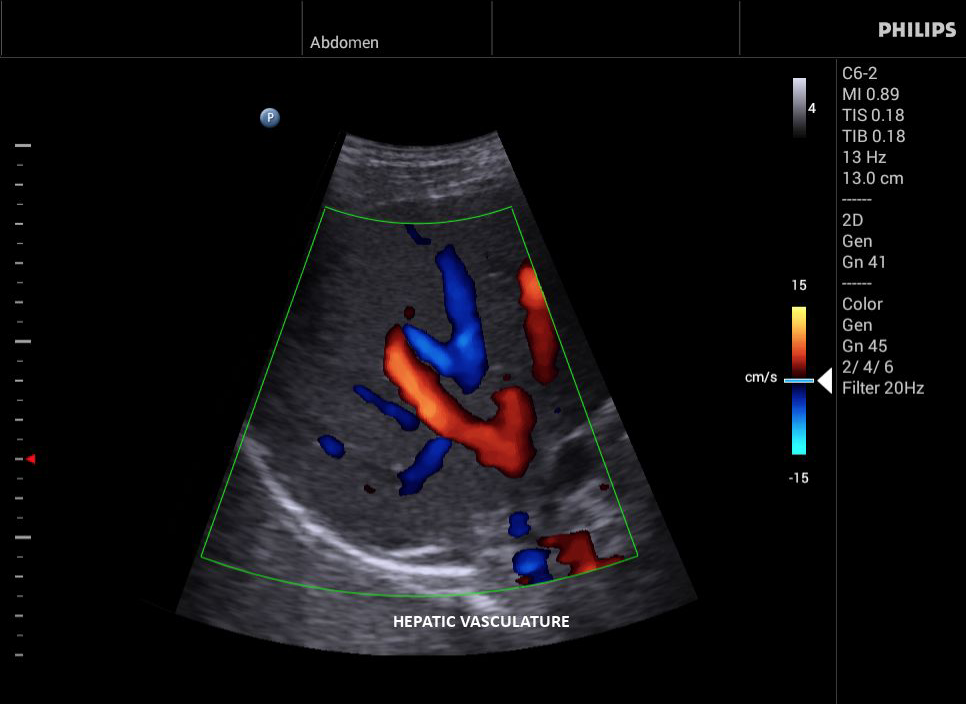

Philips InnoSight

Philips InnoSight увеличивает возможности сканирования во множестве мест оказания медицинских услуг. Благодаря данному УЗИ аппарату врачи могут не сомневаться в быстром выполнении обычных ультразвуковых сканирований во врачебном кабинете, клинике или больнице.

InnoSight позволяет перенести ультразвуковую диагностику непосредственно туда, где пациенту оказывается медицинская помощь, что повышает мобильность врачей. Этот компактный и легкий ультразвуковой аппарат позволяет чаще использовать возможности ультразвуковой диагностики и предоставляет широкий набор технологий для проведения углубленных исследований — программные пакеты для специализированного анализа, функции аннотирования и наборы готовых настроек для различных типов тканей.

Эргономичная система с высококачественными широкополосными датчиками Philips помогает повысить клиническую надежность результатов исследования и уровень оказания медицинских услуг. Аппарат можно перемещать вручную или с помощью тележки.

• Общие абдоминальные исследования;

• Исследования сосудов;

• Цветное допплеровское картирование

• Конвексный УЗИ датчик Philips С6-2